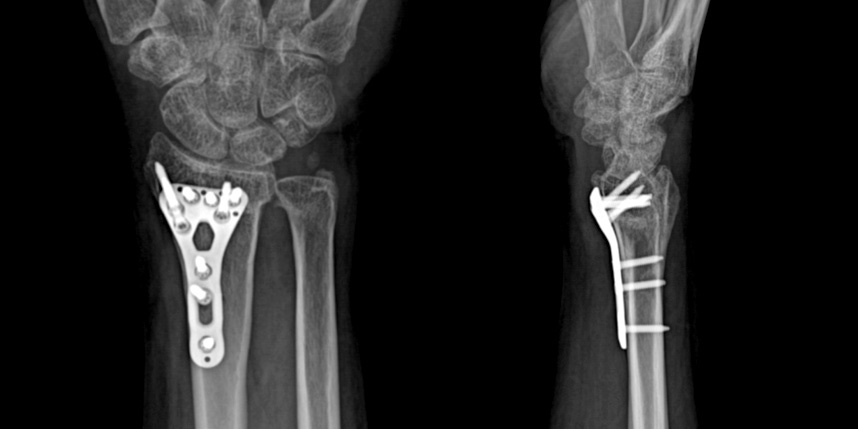

손목 골절

골절이 심하지 않은 경우에는 깁스로 고정해서 유합을 시킬 수 있으나, 정도가 심한 경우에는 손,발목 골절 수술을 진행할 수 있습니다.

골절은 정확하게 골절편을 잘 맞추고 고정하는 것이 중요합니다. 특히 관절면을 잘 맞추는 것이 중요합니다.